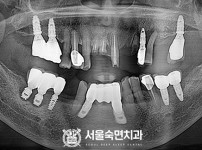

임플란트-전후사진4

치과를-선택할-때-꼭-확인하세요-서울숙면치과-임플란트-전후사진